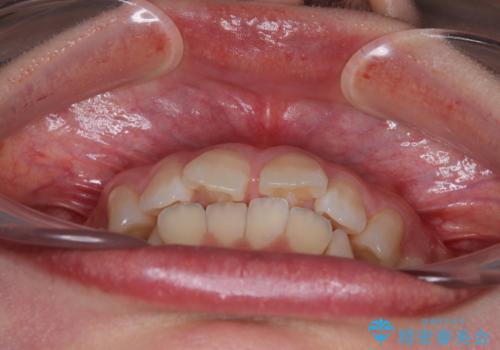

深い咬み合わせによる隙間 インビザライン矯正でコンプレックスを改善

- 上の前歯の隙間を気にして来院された患者様です。

インビザラインにより、上下の歯列を側方に拡大しつつ、前歯の隙間を閉じていくこととしました。

隙間の原因は強い咬合力や舌の突出癖、小帯の異常付着などがありますが、舌のトレーニングをしっかりと行いながら、装着時間を遵守して装着していただいたおかげで、スムーズに治療を終えることができました。